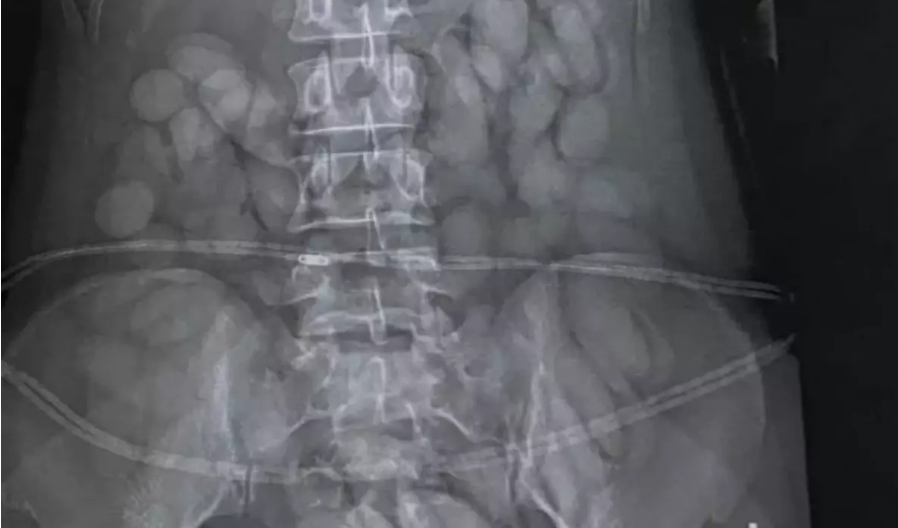

Hava limanında çəkilən rentgendə mədəsində dərman ehtiyatı aşkar edildikdə, qadın dərhal xəstəxanaya aparılıb.

Mədəsindən 60-dan çox narkotiklə doldurulmuş kapsul çıxarılan qadın həbs olunub.